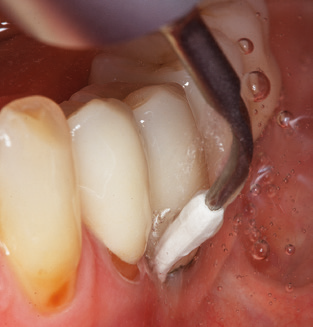

Unerlässlich für die UPT implantat prothetisch versorgter Patienten sind natürlich Arbeitsspitzen für die Reinigung von Implantatoberflächen. Der Implantatreinigungsaufsatz des hier verwendeten Systems zeichnet sich dabei durch eine spitz zulaufende sechskantige konische Form aus. Dieses Design erlaubt ein leichtes atraumatisches Eindringen in die periimplantäre Tasche und zeigt eine gute Reinigungsleistung (Abb. 7).